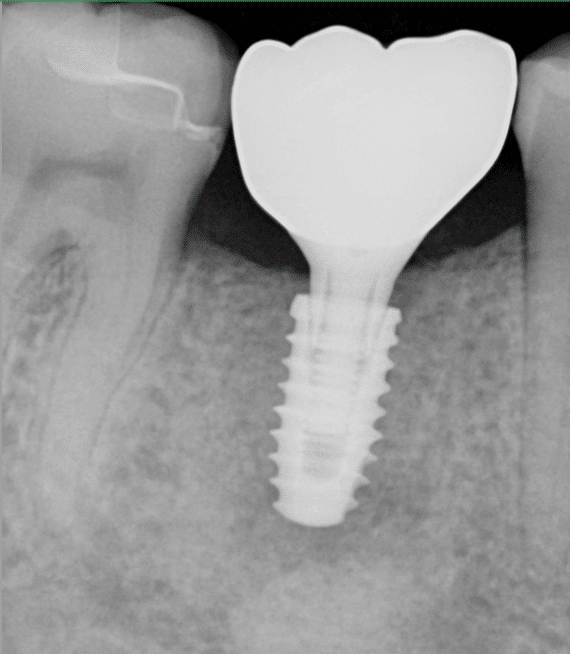

Dental implants are a permanent and safe solution to missing teeth. The implants used at Smile Vegas Dental are made of titanium, which is one of the most bio compatible materials on the market.

Implants are designed to mimic and function just like your natural tooth, as it is placed entirely in your jawbone. The process may take four to six months for the implant to fuse itself with the surrounding bone.

A prosthesis used to replace lost teeth is called a dental implant. In essence, it’s a tiny titanium post or fixture that is placed into the mandible, to which a fixed bridge, partial denture, complete denture, or single crown may be affixed. Following the implant’s integration with your bone, the prosthetic tooth or teeth are affixed to the implant via a device known as an abutment. An “implant tooth” is therefore made up of three components: the fake tooth, the abutment, and the dental implant itself.